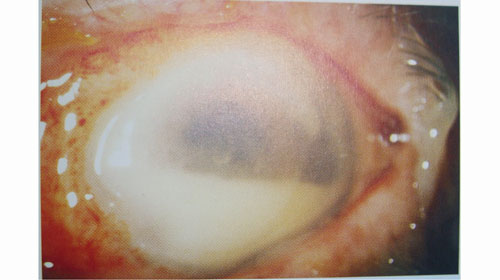

Nhân trường hợp chị Trần Thị N. (Hàm Yên, Tuyên Quang) đến Bệnh viện Mắt TW khám chữa mắt, được bác sĩ kết luận mắt phải bị viêm toàn bộ nhãn cầu (viêm toàn nhãn), tức là viêm cả tổ chức quanh mắt. Mặc dù được các bác sĩ tích cực cứu chữa nhưng do bệnh nhân đến quá muộn, mắt đã bị hoại tử hoàn toàn nên bắt buộc phải phẫu thuật múc bỏ nhãn cầu để tránh nhiễm trung máu, có thể gây tử vong. Các bác sĩ cho biết, viêm toàn nhãn là tình trạng nhiễm khuẩn nặng nề nhất trong điều trị nhãn khoa với tỷ lệ điều trị thành công là rất thấp, nhất là các trường hợp đến bệnh viện muộn như chị N., nguy cơ hỏng mắt là rất cao. Vậy, viêm nội nhãn là gì? Dấu hiệu của bệnh thế nào? Xin giới thiệu với bạn đọc thông tin liên quan đến căn bệnh nguy hiểm này:

Khi bị VNN, bệnh nhân nhìn mờ, đau nhức mắt, kích thích khó chịu cộng thêm đau đầu, sợ ánh sáng và đỏ mắt, sưng nề xung quanh mắt. Khám bác sĩ chuyên khoa mắt có thể phát hiện các dấu hiệu như: mi sưng nề, đỏ; kết mạc cương tụ; giác mạc phù, thâm nhiễm; mủ tiền phòng; viêm dịch kính, viêm gai thị; các khối mủ trắng trên hắc - võng mạc.

Viêm nội nhãn có thể gây mất thị lực trầm trọng cho khoảng 20% bệnh nhân. Sau khi được điều trị, chỉ có khoảng 55% bệnh nhân đạt được thị lực cuối cùng là 1/10 hoặc kém hơn. Riêng việc có phải múc bỏ mắt hay không còn tùy thuộc tình trạng bệnh, diễn tiến bệnh, việc đáp ứng điều trị của từng người, chỉ có bác sĩ trực tiếp điều trị mới có thể trả lời chính xác, bên cạnh việc phải thông qua một hội đồng chuyên môn để hội chẩn. Nếu bệnh nhân bị viêm nội nhãn trầm trọng, đau nhức nhiều, mủ ăn lan hết nhãn cầu... thì bắt buộc phải bỏ mắt để loại trừ vi khuẩn không lan ra chỗ khác (lên não gây viêm tắc mạch xoang hang, vào máu gây nhiễm khuẩn huyết). Nếu việc điều trị không đáp ứng với kháng sinh, thị lực của bệnh nhân sẽ khó có thể hồi phục.